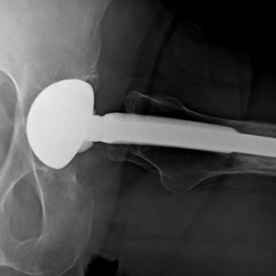

Bei einer Arthrose handelt es sich um eine Knorpelabnutzung in einem Gelenk, wobei unterschiedliche Ausprägungsgrade möglich sind. Je nach Ausprägungsart kommen konservative (Entzündungshemmende Medikamente, physikalische Therapie, orthopädische Hilfen) oder operative Verfahren (arthroskopische Spülung bzw. Gelenktoilette, Knochenumstellungen, Knorpelknochenzelltransplantationen oder prothetische Versorgung) in Frage.

Röntgenbilder